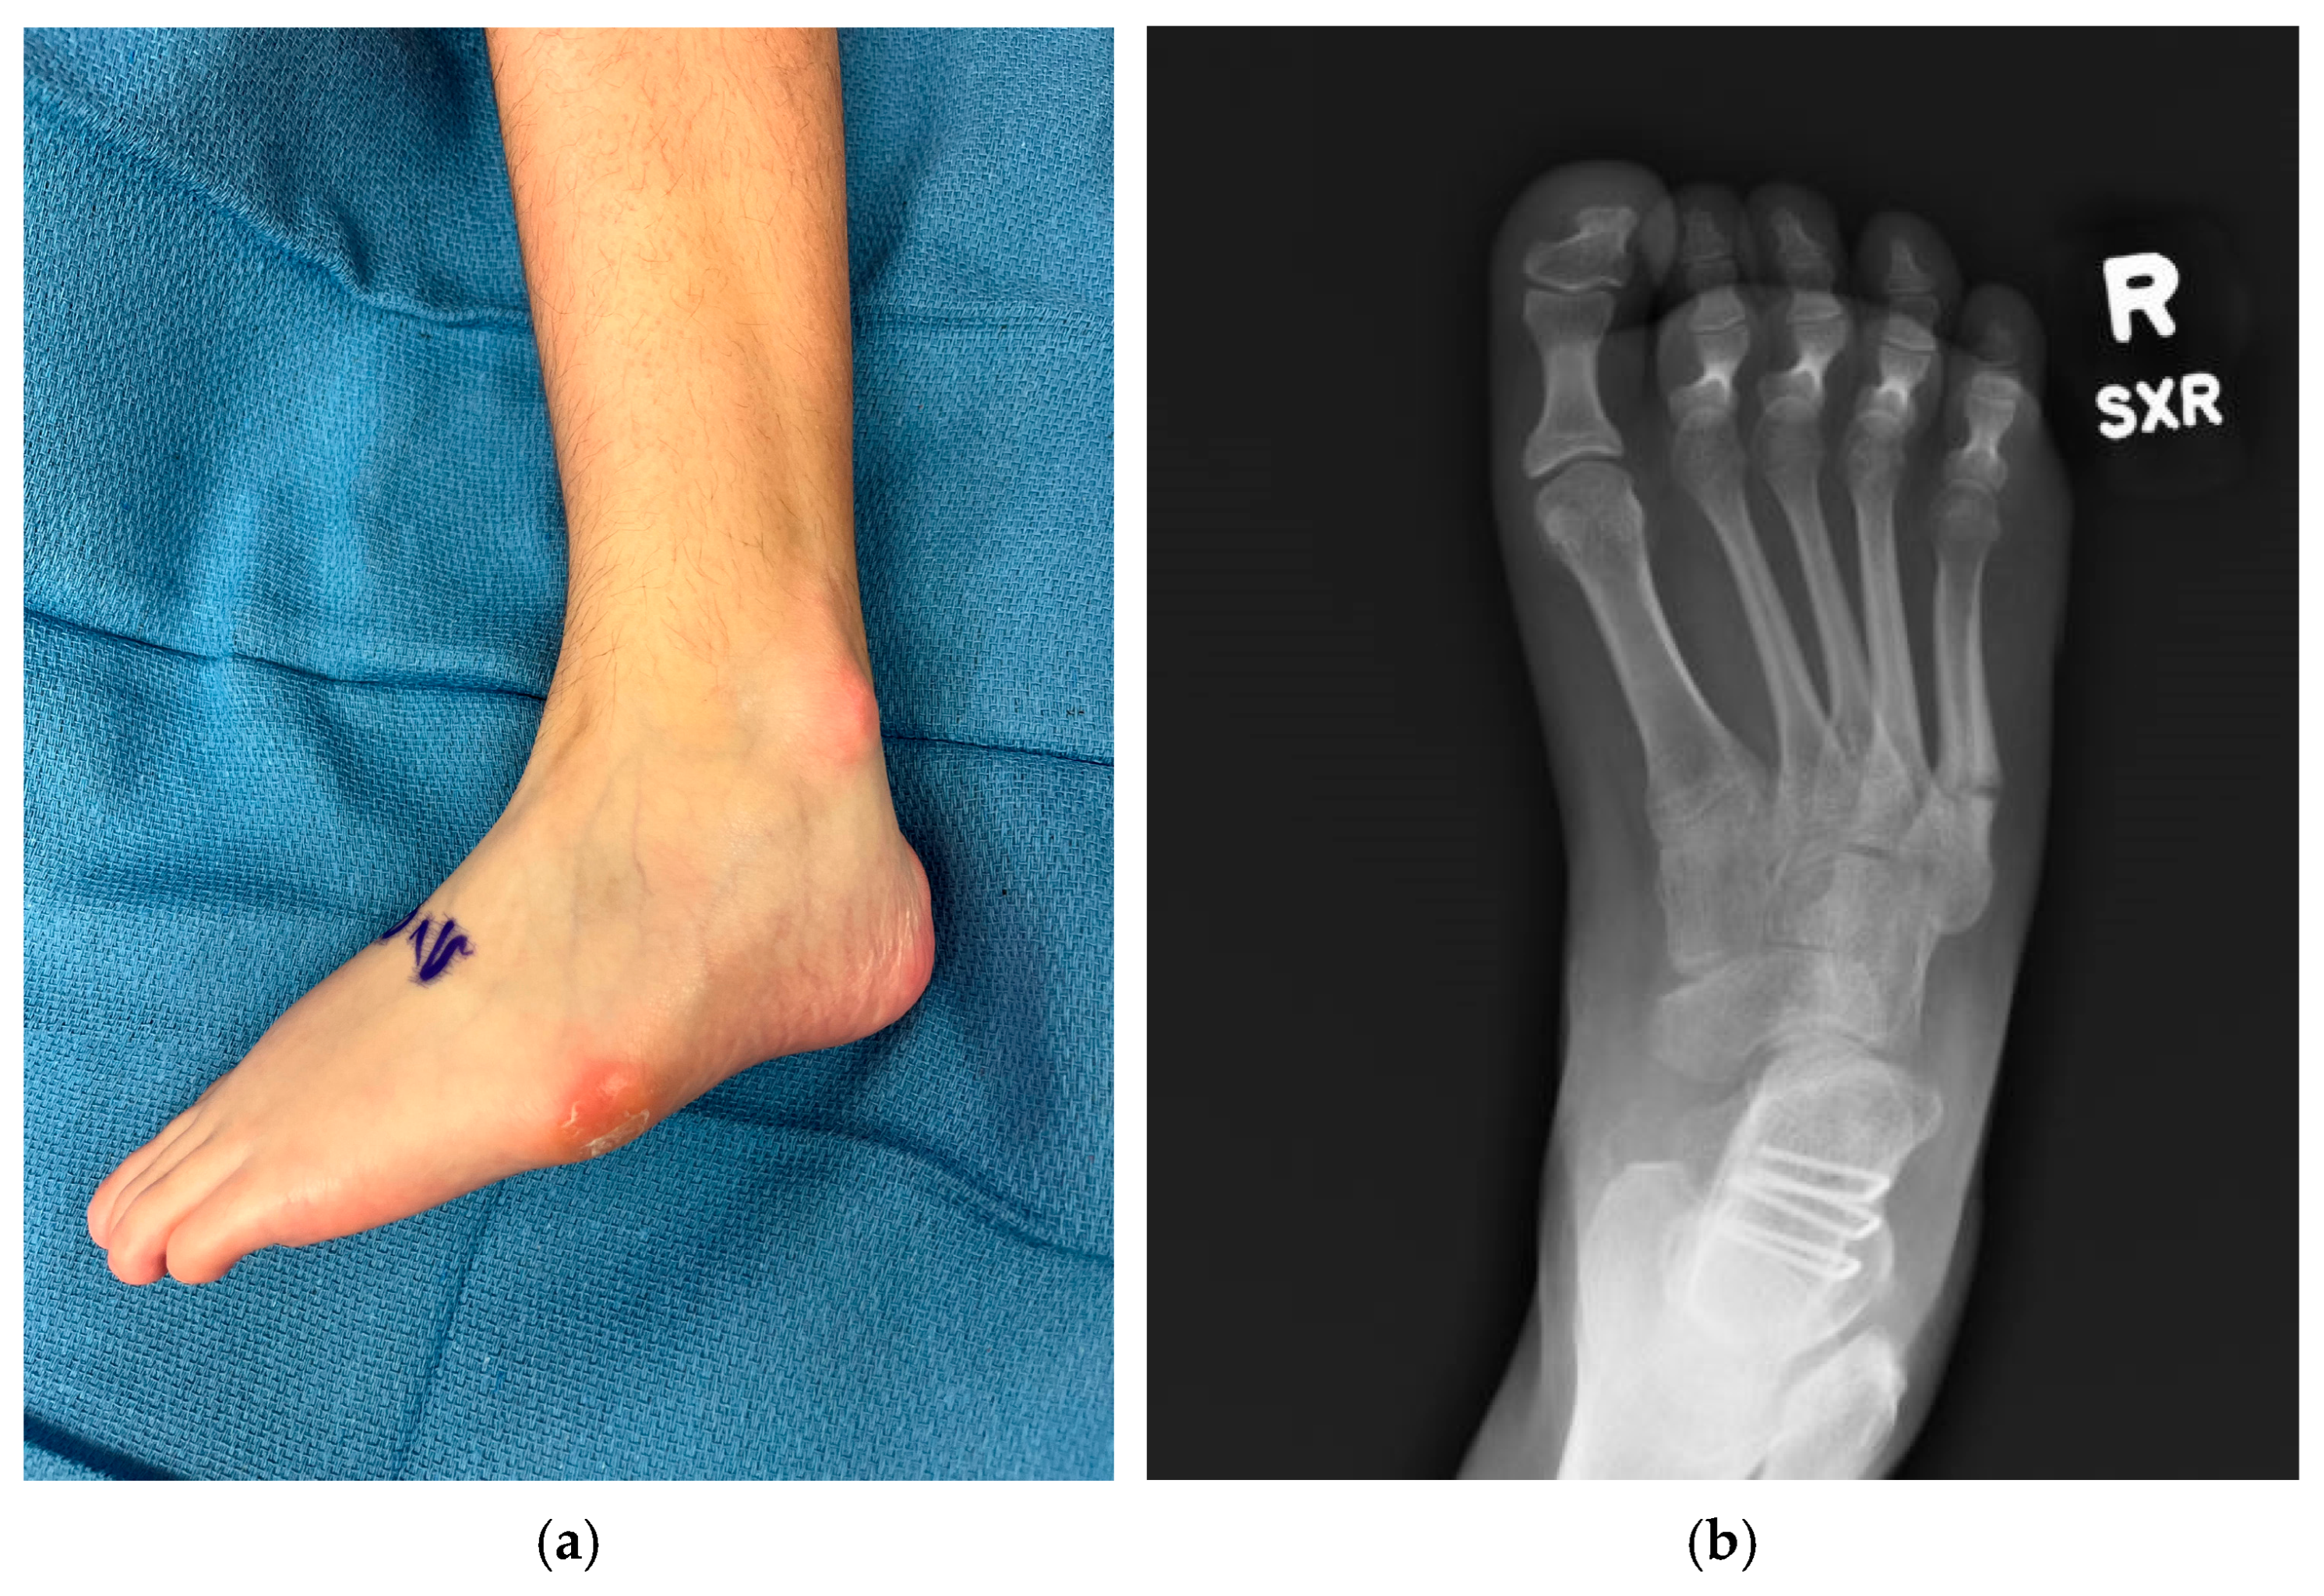

Figure 2.

Examples of negative sequelae of varus foot deformities. (a) Varus foot with evidence of skin breakdown at base of 5th metatarsal and lateral malleolus from poor bracing tolerance, 13-year-old female; (b) 5th metatarsal base fracture in a 17-year-old female.